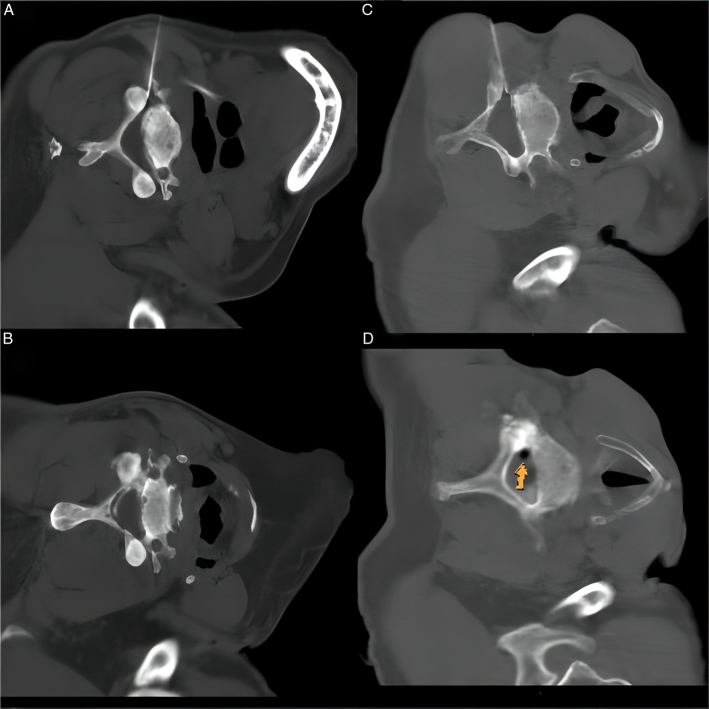

Computed Tomography-Guided Dorsal Root Ganglion Ozone Injection Combined With Pulsed Radiofrequency for Acute Herpes Zoster Neuralgia Treatment of Middle-aged and Elderly People: A Randomized, Double-blinded, Controlled Trial.

Objectives: To investigate the efficacy and safety of pulsed radiofrequency of the dorsal root ganglion combined with ozone injection for treating acute herpes zoster (HZ) neuralgia in middle-aged and elderly adults.

Methods: A total of 164 middle-aged and elderly patients with acute HZ were randomly assigned to 2 groups: the pulsed radiofrequency combined with ozone injection group (group A) and the pulsed radiofrequency group (group B). The therapeutic effects were evaluated using Numeric Rating Scale (NRS) scores and the average doses of gabapentin (mg/d) preoperatively and 1 day, 2 weeks, 4 weeks, 12 weeks, and 24 weeks postoperatively. The incidence of clinically significant postherpetic neuralgia (PHN) and complications in the 2 groups were recorded.